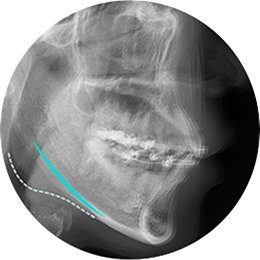

At id Hospital, we use 3D-CT scans to determine the optimal amount and location of bone cuts for the best results, while avoiding damage to the facial nerves.

With our diagonal osteotomy technique, we move a larger portion of the cheekbone toward the back and side, delivering visible results from every angle.

First of all, it is important to accurately analyze the shape of the cheekbones before surgery. It is necessary to consult with a clinician who has a lot of clinical experiences based on the results of X-ray and 3D-CT. At surgery, cheekbones are shaved based on the diagnosis. Depending on the skin elasticity of the person, an additional lifting procedure may also be recommended so the tissues are lifted together to give a lifting effect.